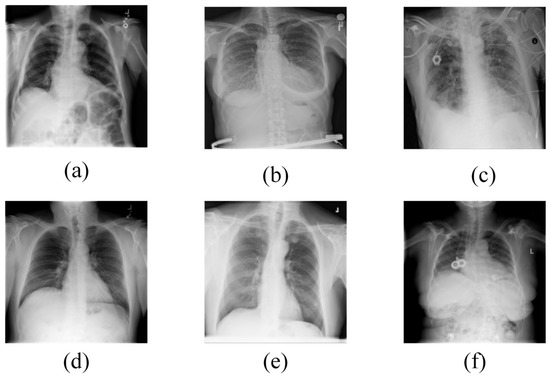

The Chest X-ray14 dataset contains a total of 112,120 X-ray images, representing 14 different types of lung diseases. For our experiments, we selected six common lung diseases: Atelectasis (2564 images), Effusion (2406 images), Infiltration (2296 images), Mass (1302 images), Nodule (1646 images), and Pneumothorax (1335 images), along with 10,711 normal lung images. The dataset is divided into a training set of 15,582 images, a validation set of 2226 images, and a test set of 4452 images. Examples of these six types of lung conditions are shown in Figure 7. This dataset’s heterogeneity arises from the presence of multiple lung conditions in single images, which can complicate the classification task.